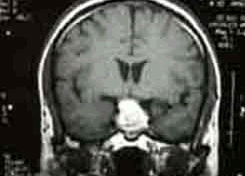

蛛網膜下腔出血(SAH)是指各種原因引起的腦血管突然破裂,血液流至蛛網膜下腔所致。檢查

1.病因治療 蛛網膜下腔出血的根本治療。動脈瘤的直接夾閉不僅能防止再出血,也為以後的血管痙攣治療創造條件。

自發性蛛網膜下腔出血CT圖血管痙攣也是蛛網膜下腔出血病人致死致殘的主要原因,約有13.5%的動脈瘤破裂引起的蛛網膜下腔出血病人因血管痙攣而死亡或殘廢。在致殘病人中約39%因血管痙攣而引起。